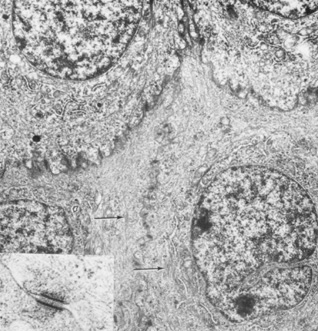

The corneal epithelium is the anterior-most cell layer of the cornea (Fig. 1). It is typically several cell layers thick, consisting of the apical cell squamous layer, the multilayered, polygonal-shaped wing cells beneath the apical layer, and the posterior-most layer of basal cells (Fig. 2). The wing cell layer is two or three cells thick in the central cornea, but tends to be four to five cells thick in the periphery. In total, the epithelium is approximately 50 μm thick in the central human cornea.

Fig. 1. Full-thickness view of the normal human cornea. From top: epithelium, Bowman's layer (arrow), stroma, Descemet's membrane (arrow), and endothelium (hematoxylin-eosin stain, 80×). (Courtesy of Drs. Rodrigues, Waring, Hackett, and Donohoo.)

Fig. 2. Full-thickness electron micrograph of corneal epithelium. Note the cell shape change with depth, the variation of cell membrane interdigitation, and the intracellular differences between cell types. S, apical surface cells; W, wing cells; and B, basal cells. Also note the microvilli seen along the apical membrane of the surface cells (3,620×). Inset: Epithelium (E) overlies a thin, dense basement membrane (arrow) with no discernible laminar appearance (periodic acid-Schiff [PAS] stain, 330×). (Courtesy of Drs. Rodrigues, Waring, Hackett, and Donohoo.)